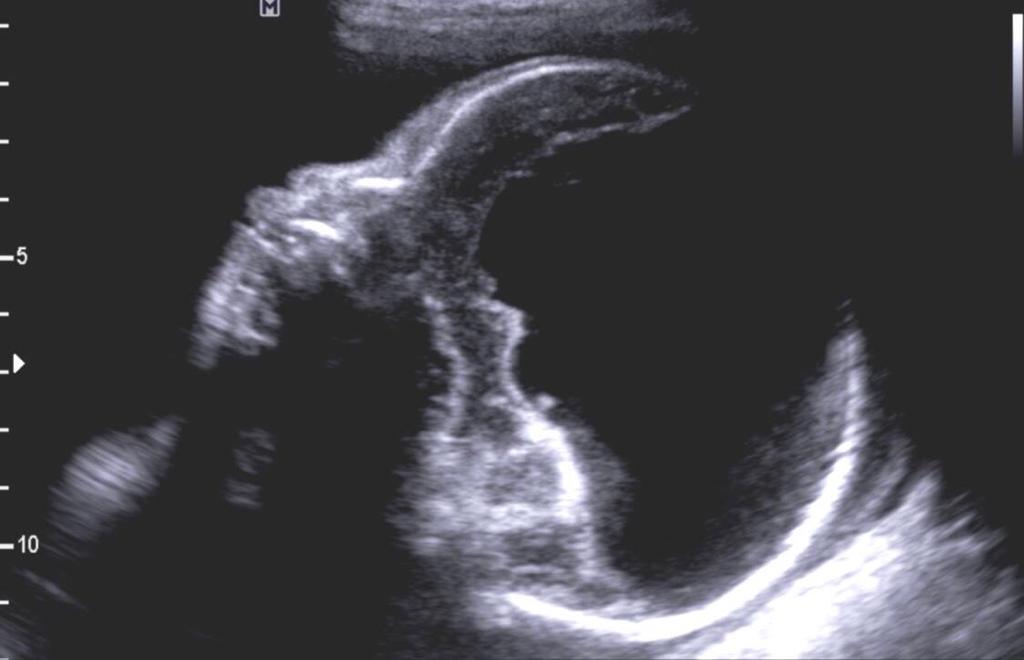

Holoprosencefalia alobar

Se caracteriza por marcados alteraciones en la línea media del encéfalo y/o malformaciones faciales.

- Fusion completa de los hemisferios cerebrales

- Ausencia de la fisura interhemisferica y de la hoz cerebral

- Agenesia del cuerpo calloso y de la comisura anterior

- Holoventriculo, quiste dorsal

- Ausencia de septum pellucidum

- Los ganglios de la base de tálamos pueden estar diferenciados, funcionado o ausentes